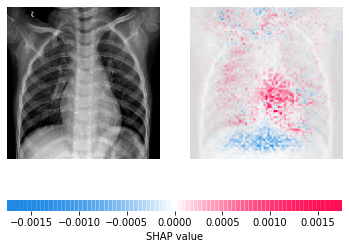

In a follow-up study published in 2018, Google Health demonstrated an important point in how AI systems can be used within the clinical environment. Through the use of AI as an initial screening tool alongside physician assessments of the same images, model predictions can be effective in helping physicians catch pathology they might have otherwise missed. The retinal image shown above shows an image with severe disease, a finding missed by two of three doctors who graded it without seeing the prediction of the model.

Similarly, physicians and AI can work together to provide more accurate assessments than either individually. The image below shows a retinal scan labeled as having moderate retinopathy. Without assistance, two of the three care providers reading the scan would have diagnosed it as "no disease," and the patient might miss needed care from a specialist.

Using these datasets, a number of Deep Learning models have emerged that are capable of screening for lung disorders with high accuracy. These models are able to encode features of disease and detect specific conditions, even when other pathologies may be present, and have shown promise for building systems capable of aiding with triage.

COVID researchers have been able to build upon this work to create new models capable of detecting infections with high accuracy and differentiating between COVID-19 and non-COVID pneumonia. They have combined the data available from ChestX-ray8 (and other databases such as ChestX-ray14) with COVID-19 scans to create new public datasets. They have applied the lessons learned from previous work and not only created models capable of screening for disease but also prognostic models to try and determine risk for severe outcomes such as death, need for ICU admission, or ventilation.